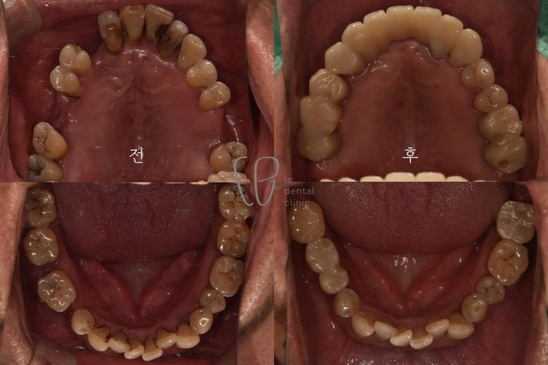

Dental Treatments in Seoul, South Korea Before and After Photos

Le Dental Clinic maintains a gallery showcasing before-and-after photos of various Dental Treatment in Seoul, South Korea, including esthetic treatments, orthodontics, and implant surgeries. These images highlight the clinic's success in transforming smiles and improving dental health.

Before and After Dental Treatment in Seoul, South Korea